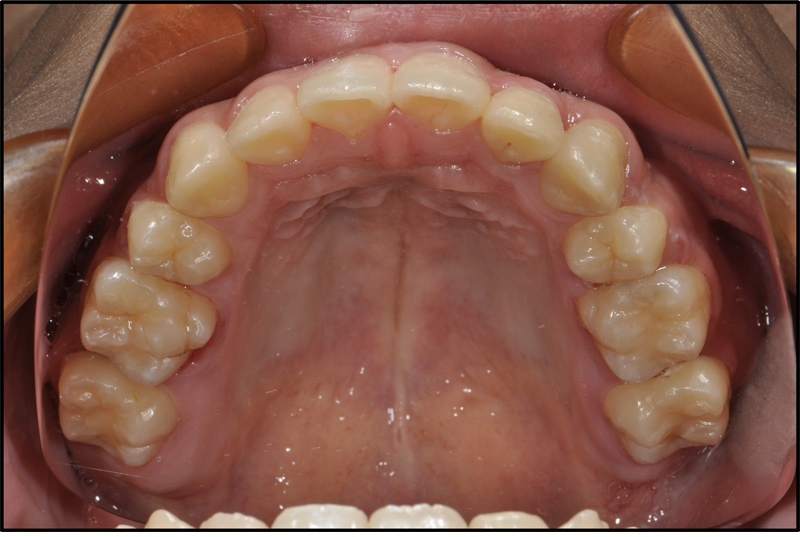

CASE 4 19歳 男

| 悩み | 前歯の歯並びが気になる。 |

|---|---|

| 抜歯 | 上下小臼歯4本、下大臼歯2本 |

| 装置 | マルチブラケット(表)、トランスパラタルアーチ |

| 内容 | 前歯にガタガタがあり歯の角度が前に傾斜していたため抜歯を選択し、さらに神経を抜いてある下顎第二大臼歯を抜歯してその部位に親知らずを並べる治療を行なった。前歯がきれいに配列され、治療済みの歯も無くなった。 |

| 期間 | 4年 |

| リスク | う蝕、歯周病、歯根吸収、治療の長期化 |

| 費用 | 70万円(調整料は含みません) |